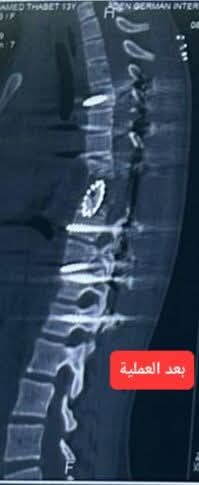

وكانت الطفلة قد وُلدت بعيب خلقي نادر في الفقرة الصدرية الثامنة، تمثل بوجود نصف فقرة فقط وغياب النصف الآخر، ما تسبب في انحناء أمامي حاد بزاوية 90 درجة، إضافة إلى جنف جانبي معقد، ودوران شديد للفقرات والضلوع، وحدبة بارزة سببت لها آلاماً مزمنة.

العملية شملت تحرير الحبل الشوكي، واستئصال الفقرة المشوّهة مع أجزاء من الفقرتين السابعة والتاسعة، وزراعة فقرة صناعية، إلى جانب تثبيت العمود الفقري بواسطة 18 مسماراً طبياً. كما تميّز التدخل بتصحيح الاعوجاجات المتعددة وإعادة التوازن للعمود الفقري بدرجة قريبة من الوضع الطبيعي.

وأكد الدكتور عمر التركي، إن الطفلة وُلدت بعيب خلقي نادر في الفقرة الصدرية الثامنة، حيث وُجد نصف فقرة فقط مع غياب النصف الآخر، ما أدى إلى نمو غير طبيعي للعمود الفقري، تسبب في انحناء أمامي حاد بزاوية 90 درجة، وجَنَف جانبي معقد، وانزياحات متعددة، إضافة إلى دوران شديد للفقرات وحدبة بارزة.

وأوضح التركي أنه وبعد تشخيص دقيق ودراسة مستفيضة للحالة، قمت - بعون الله وتوفيه - ومعي الفريق الجراحي بعمل العملية النوعية والتي شملت تعديل وتصحيح اعوجاج العمود الفقري المتعدد والمعقد، وتحرير الحبل الشوكي، واستئصال الفقرة المشوّهة مع أجزاء من الفقرتين السابعة والتاسعة، وزراعة فقرة صناعية، وتثبيت العمود الفقري وتعديله بواسطة 18 مسماراً طبياً.